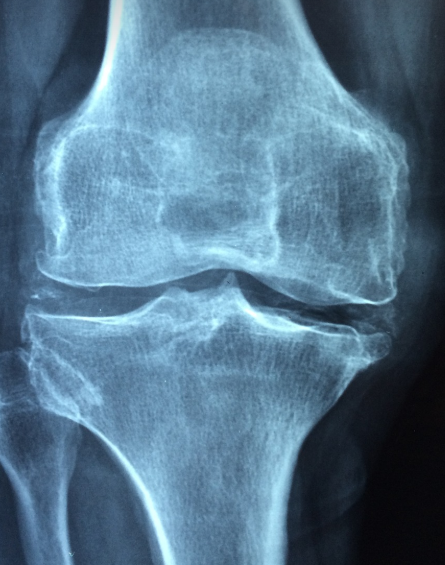

골다공증 원인부터 고관절 위험까지, 당신이 꼭 알아야 할 모든 것

골다공증 원인부터 고관절 위험까지, 당신이 꼭 알아야 할 모든 것혹시 뼈 건강을 소홀히 하고 계신가요? "생로병사의 비밀" TV프로그램에서 골다공증에 대해 나왔습니다. 골다공증은 조용히 진행되지만 한순간의 골절로 큰 문제가 될 수 있습니다. 골다공증은 증상이 거의 없지만, 한 번 골절이 발생하면 회복이 어려운 무서운 질환입니다. 건강한 미래를 위해 지금부터 골다공증에 신경 써야겠습니다.목차1. 골다공증의 주요 원인 2. 골다공증의 증상과 조기 발견 3. 골다공증 예방을 위한 생활 습관 4. 골다공증 치료 방법 5. 고관절 골절과 골다공증의 관계 6. 뼈 건강을 위한 영양과 식단골다공증의 주요 원인 골다공증은 여러 가지 원인으로 발생하지만, 가장 중요한 요인은 나이와 호르몬 변화입니다. 특히 폐경 이후 여..